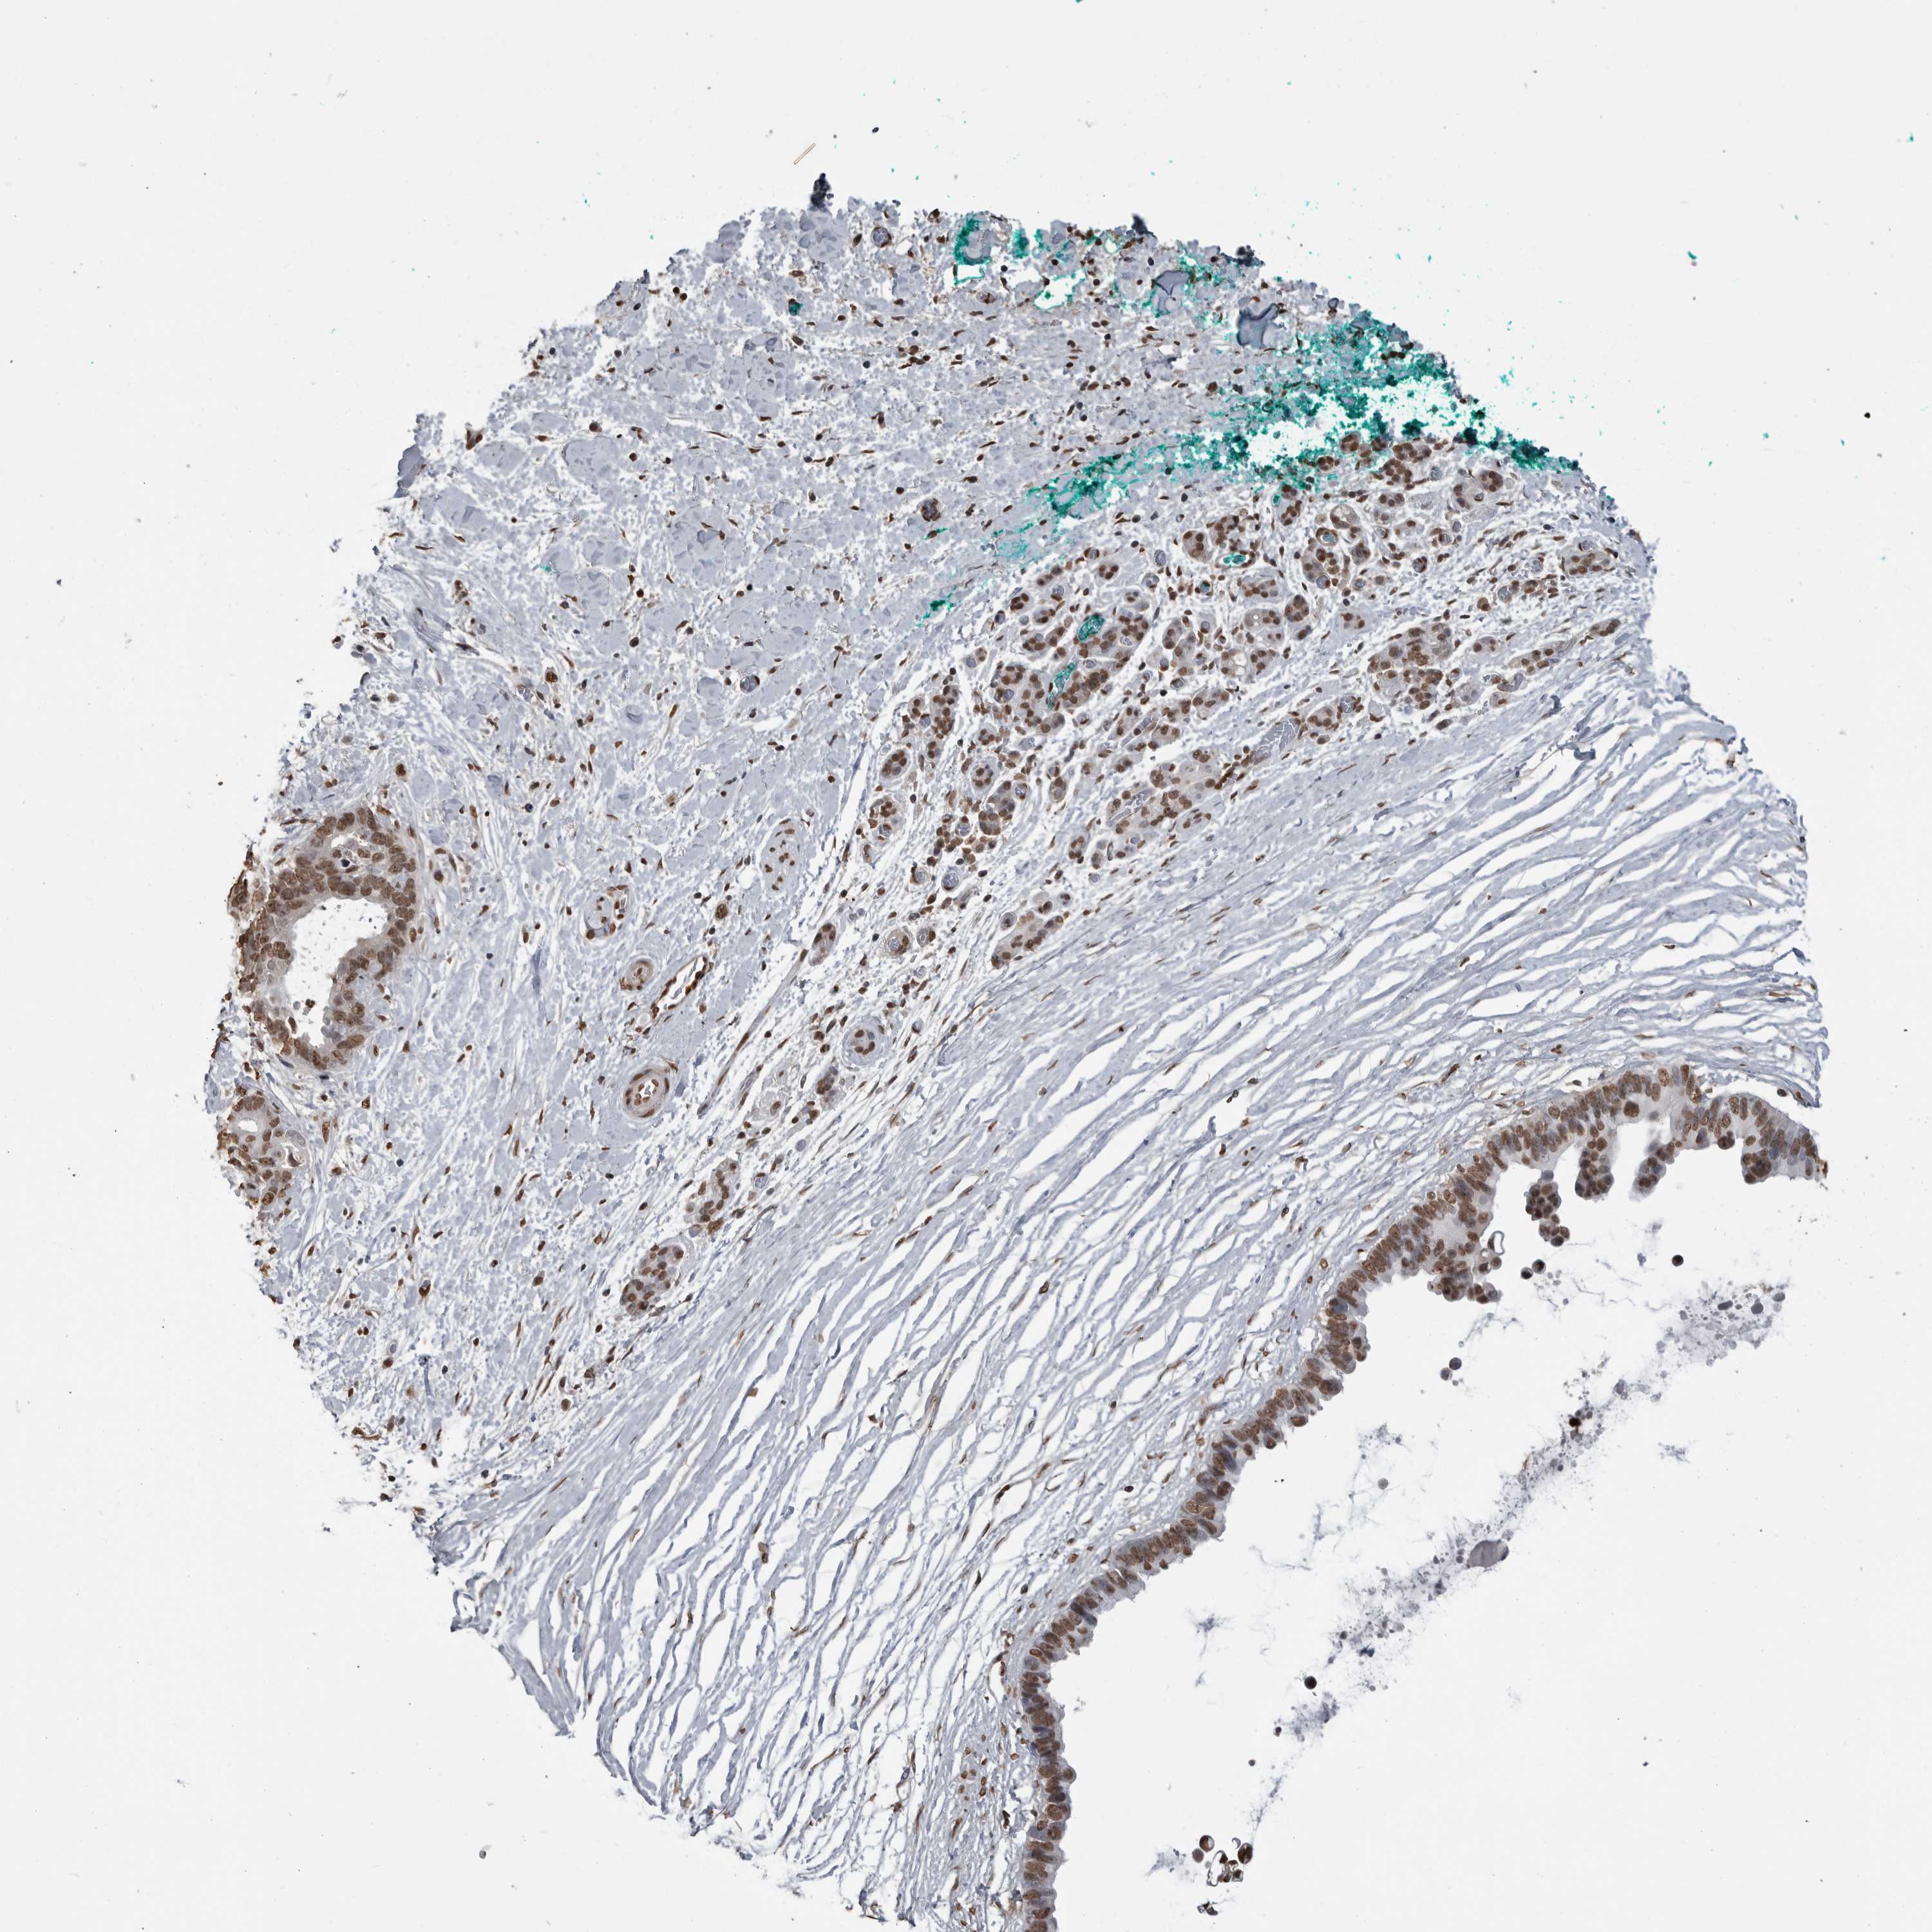

PANCREATIC CANCER - Protein expressioni

A mouse-over function shows sample information and annotation data. Click on an image to view it in a full screen mode. Samples can be filtered based on level of antibody staining by selecting one or several of the following categories: high, medium, low and not detected. The assay and annotation is described here.

Note that samples used for immunohistochemistry by the Human Protein Atlas do not correspond to samples in the TCGA dataset.

Antibody stainingi

Antibody staining in the annotated cell types in the current human tissue is reported as not detected, low, medium, or high, based on conventional immunohistochemistry profiling in selected tissues. This score is based on the combination of the staining intensity and fraction of stained cells.

Each image is clickable and will lead to virtual microscopy that enables deeper exploration of all samples and also displays staining intensity scores, fraction scores and subcellular localization as well as patient and tissue information for each sample.

Antibody HPA067203

Antibody CAB025507

Antibody CAB073546

Staining

High

Medium

Low

Not detected

Intensity

Strong

Moderate

Weak

Negative

Quantity

>75%

75%-25%

<25%

None

Location

Nuclear

Cytoplasmic/membranous

Cytoplasmic/membranous,nuclear

Adenocarcinoma, NOS